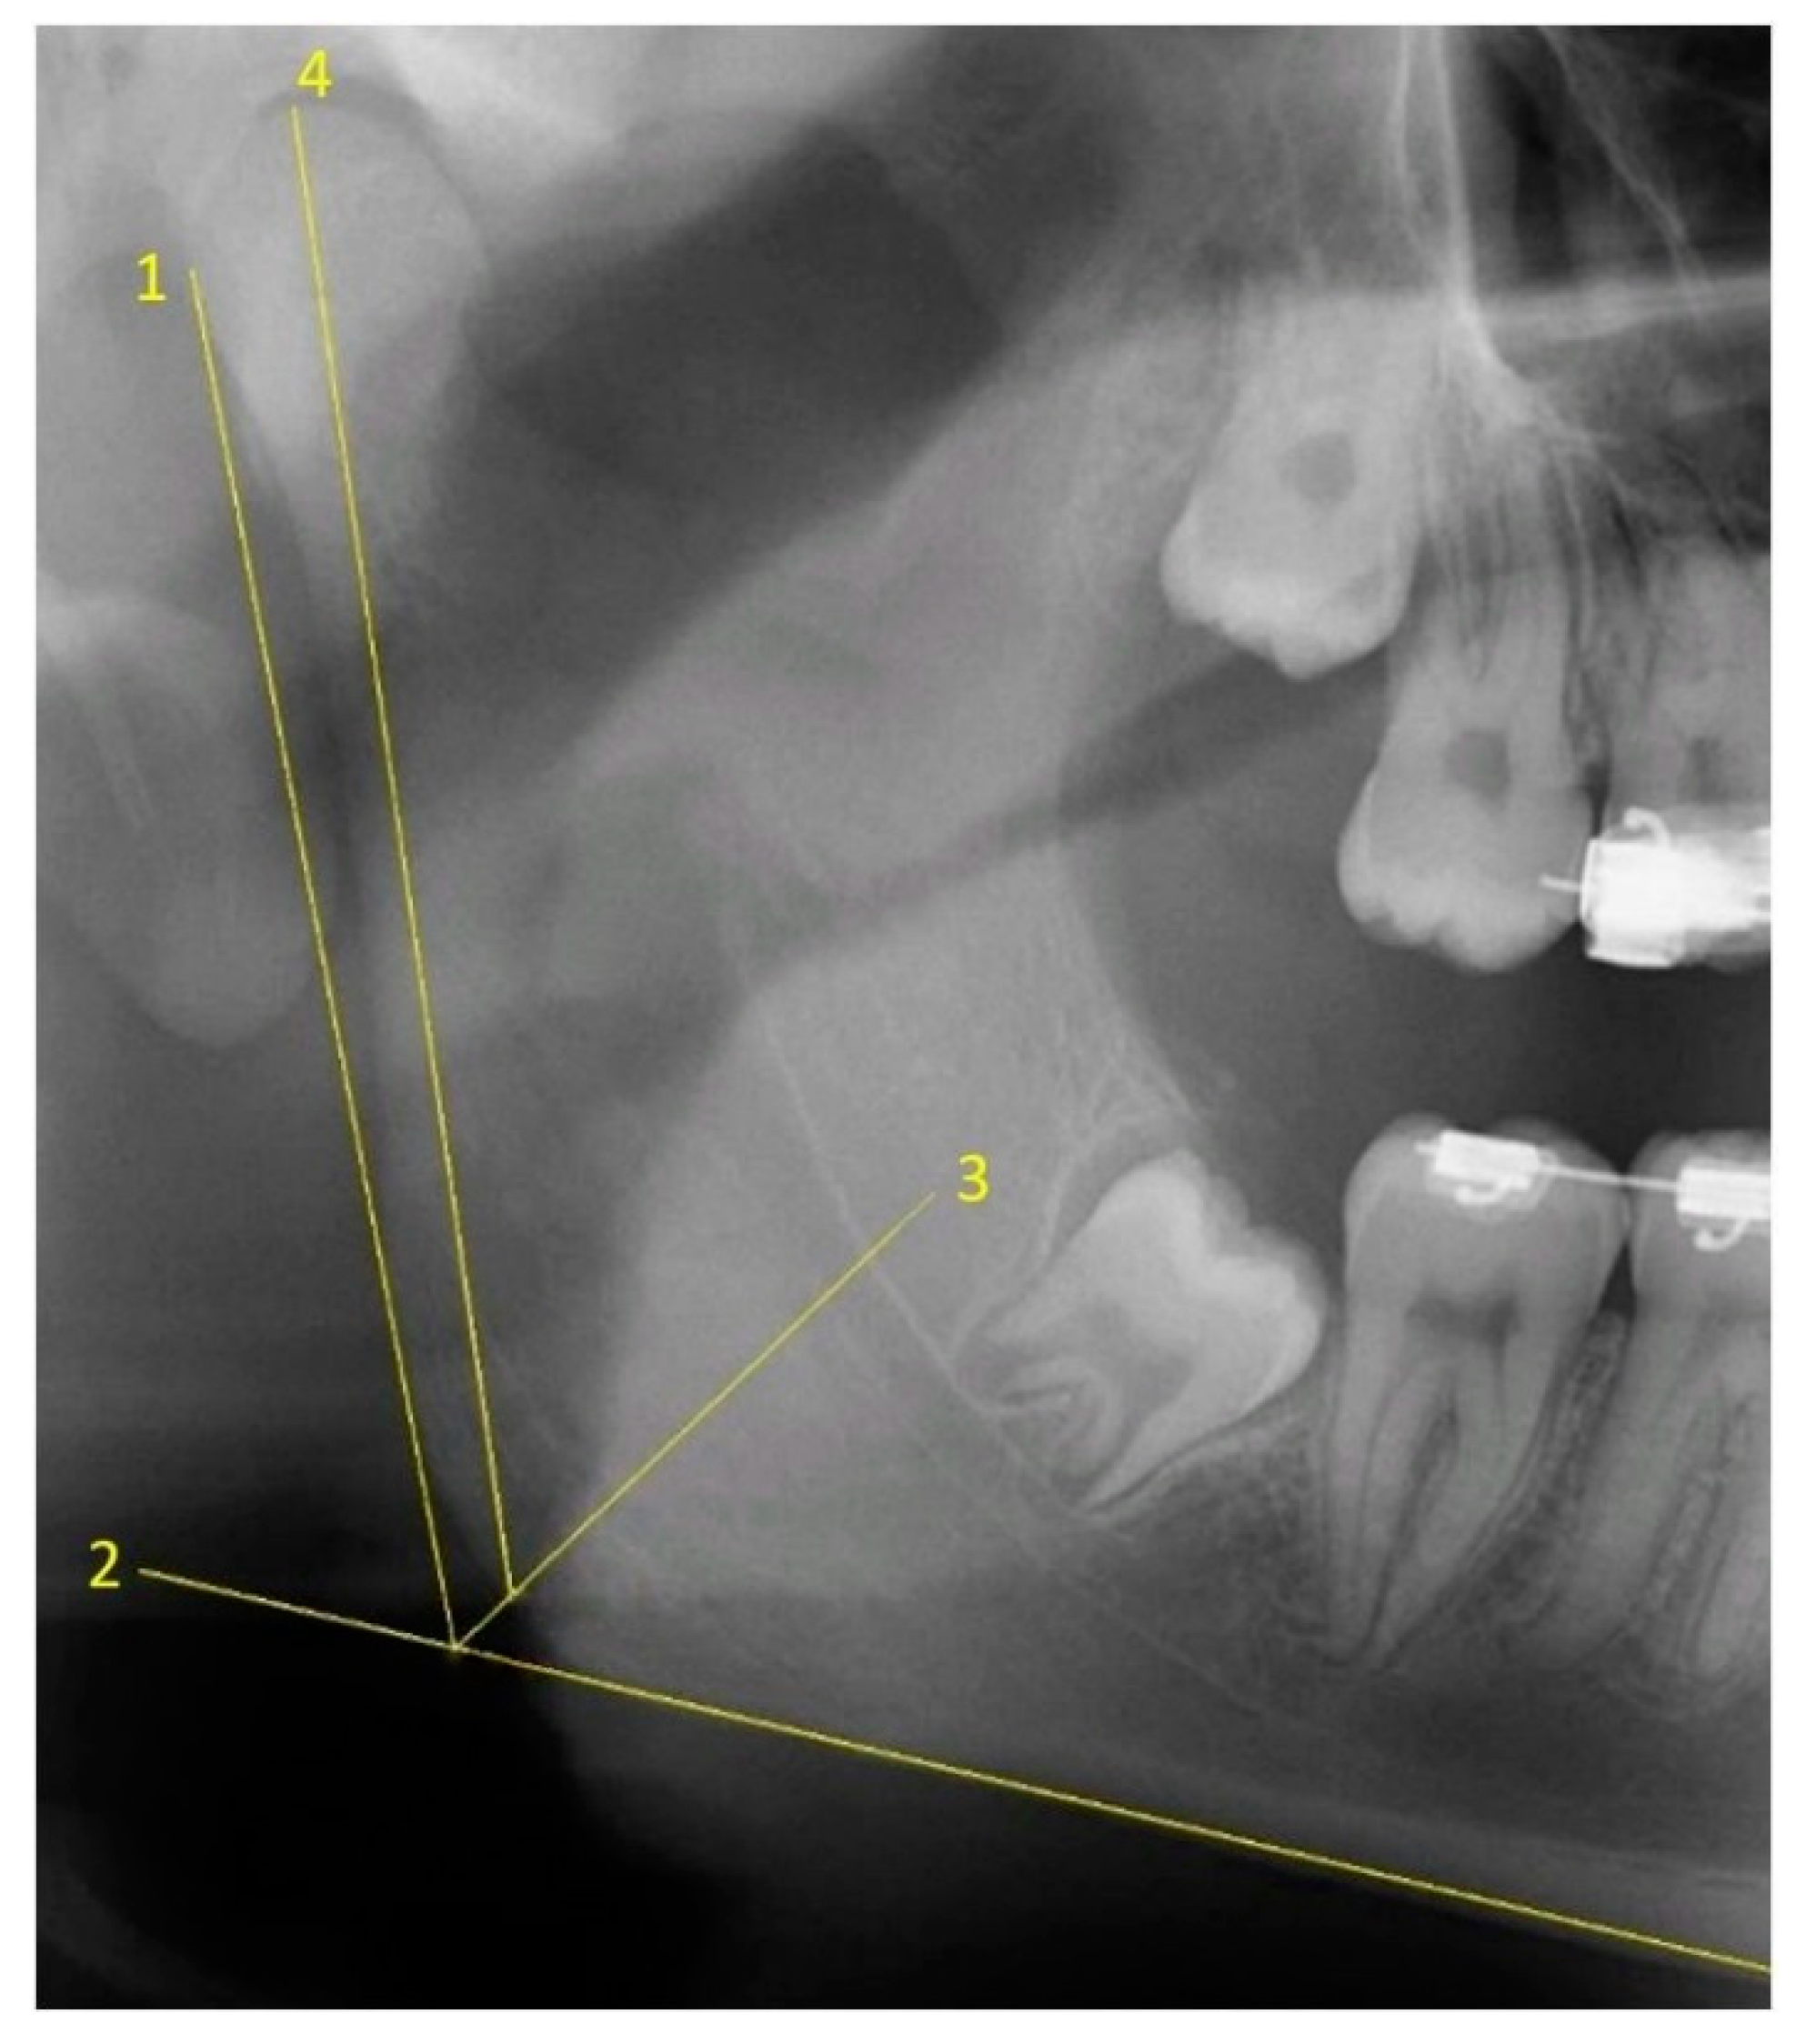

2.1. Two-Dimensional Methods